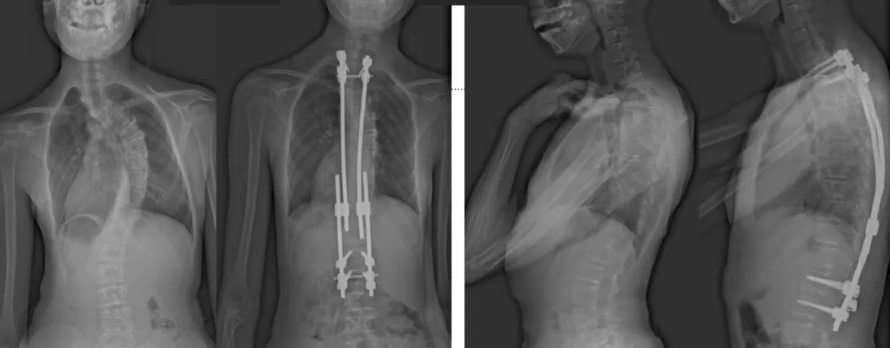

白瑪?shù)恼恍g(shù)前、術(shù)后對比圖(左側(cè));側(cè)位術(shù)前、術(shù)后對比圖(右側(cè))

白瑪今年10歲,正在讀小學(xué)。媽媽發(fā)現(xiàn),白瑪經(jīng)常歪著肩膀,在反復(fù)提醒“站直了,別歪著”后,情況也沒有改善。近半年來,白瑪?shù)挠覀?cè)肩胛骨逐漸向后凸出。到醫(yī)院檢查后發(fā)現(xiàn),白瑪?shù)男刈荡嬖诿黠@的側(cè)凸畸形,是早發(fā)型特發(fā)性脊柱側(cè)凸。由于側(cè)凸較為嚴(yán)重,已經(jīng)失去了支具治療的機(jī)會。小白瑪才10歲,隨著身體的不斷成長,她的脊柱會越來越彎,肩膀會越來傾斜。這不僅影響體態(tài)和外觀,也可能限制心、肺等內(nèi)臟器官的發(fā)育,導(dǎo)致心肺功能下降、肢體活動不便,出現(xiàn)癱瘓,甚至死亡。對于白瑪這種情況,只能利用手術(shù)治療來矯正脊柱、阻止骨骼畸形進(jìn)展。

術(shù)后第二天,白瑪就下地活動了。媽媽驚喜地發(fā)現(xiàn),白瑪一下子“長高”了近十厘米,重新抬起了頭,挺直了脊梁,肩膀也不歪了,可謂“脫胎換骨”。媽媽激動地錄制了一段白瑪走路的身影,把喜悅分享給全家。白瑪?shù)男g(shù)后檢查也提示,手術(shù)成功,恢復(fù)良好。